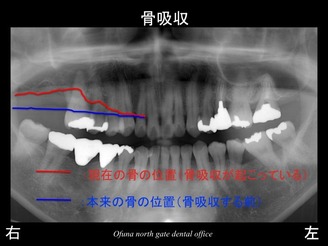

いつものように 骨吸収の状態を分かりやすくするために

骨吸収の状態を線で書いたのが以下のレントゲンになります。

青線が骨吸収を起こす前の骨の位置です。

赤線は、現在の骨の位置です。

さらに分かりやすくするために 骨吸収部位を赤色の領域で表します。

骨吸収が非常に進行しているのが分かるかと思います。